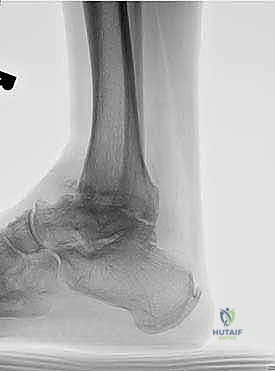

عملية تثبيت مفصل الكاحل والقدم الخلفية، والمعروفة طبياً بـ (Tibiotalocalcaneal Arthrodesis)، هي إجراء جراحي معقد يهدف إلى دمج (لحام) ثلاثة عظام رئيسية معاً لتكوين كتلة عظمية واحدة صلبة وغير متحركة. هذه العظام هي: عظمة الساق الكبرى (Tibia)، وعظمة الكاحل (Talus)، وعظمة الكعب (Calcaneus).

يتم هذا الدمج باستخدام مسمار نخاعي (Intramedullary Nail) طويل وقوي يُدخل من أسفل الكعب ليخترق العظام الثلاثة، ويتم تثبيته ببراغي قفلية لضمان أقصى درجات الثبات. الهدف من إلغاء الحركة في هذه المفاصل التالفة هو القضاء التام على الاحتكاك العظمي الذي يسبب الألم المبرح، مما يوفر للمريض قاعدة ثابتة وقوية للمشي.

يعتمد الدكتور هطيف على الأشعة السينية (X-rays) والأشعة المقطعية (CT Scans) ثلاثية الأبعاد لبناء خريطة دقيقة للتشوهات العظمية وتحديد حجم ومسار المسمار النخاعي المناسب لكل مريض بدقة متناهية. يتم مناقشة كل هذه التفاصيل بشفافية تامة مع المريض.